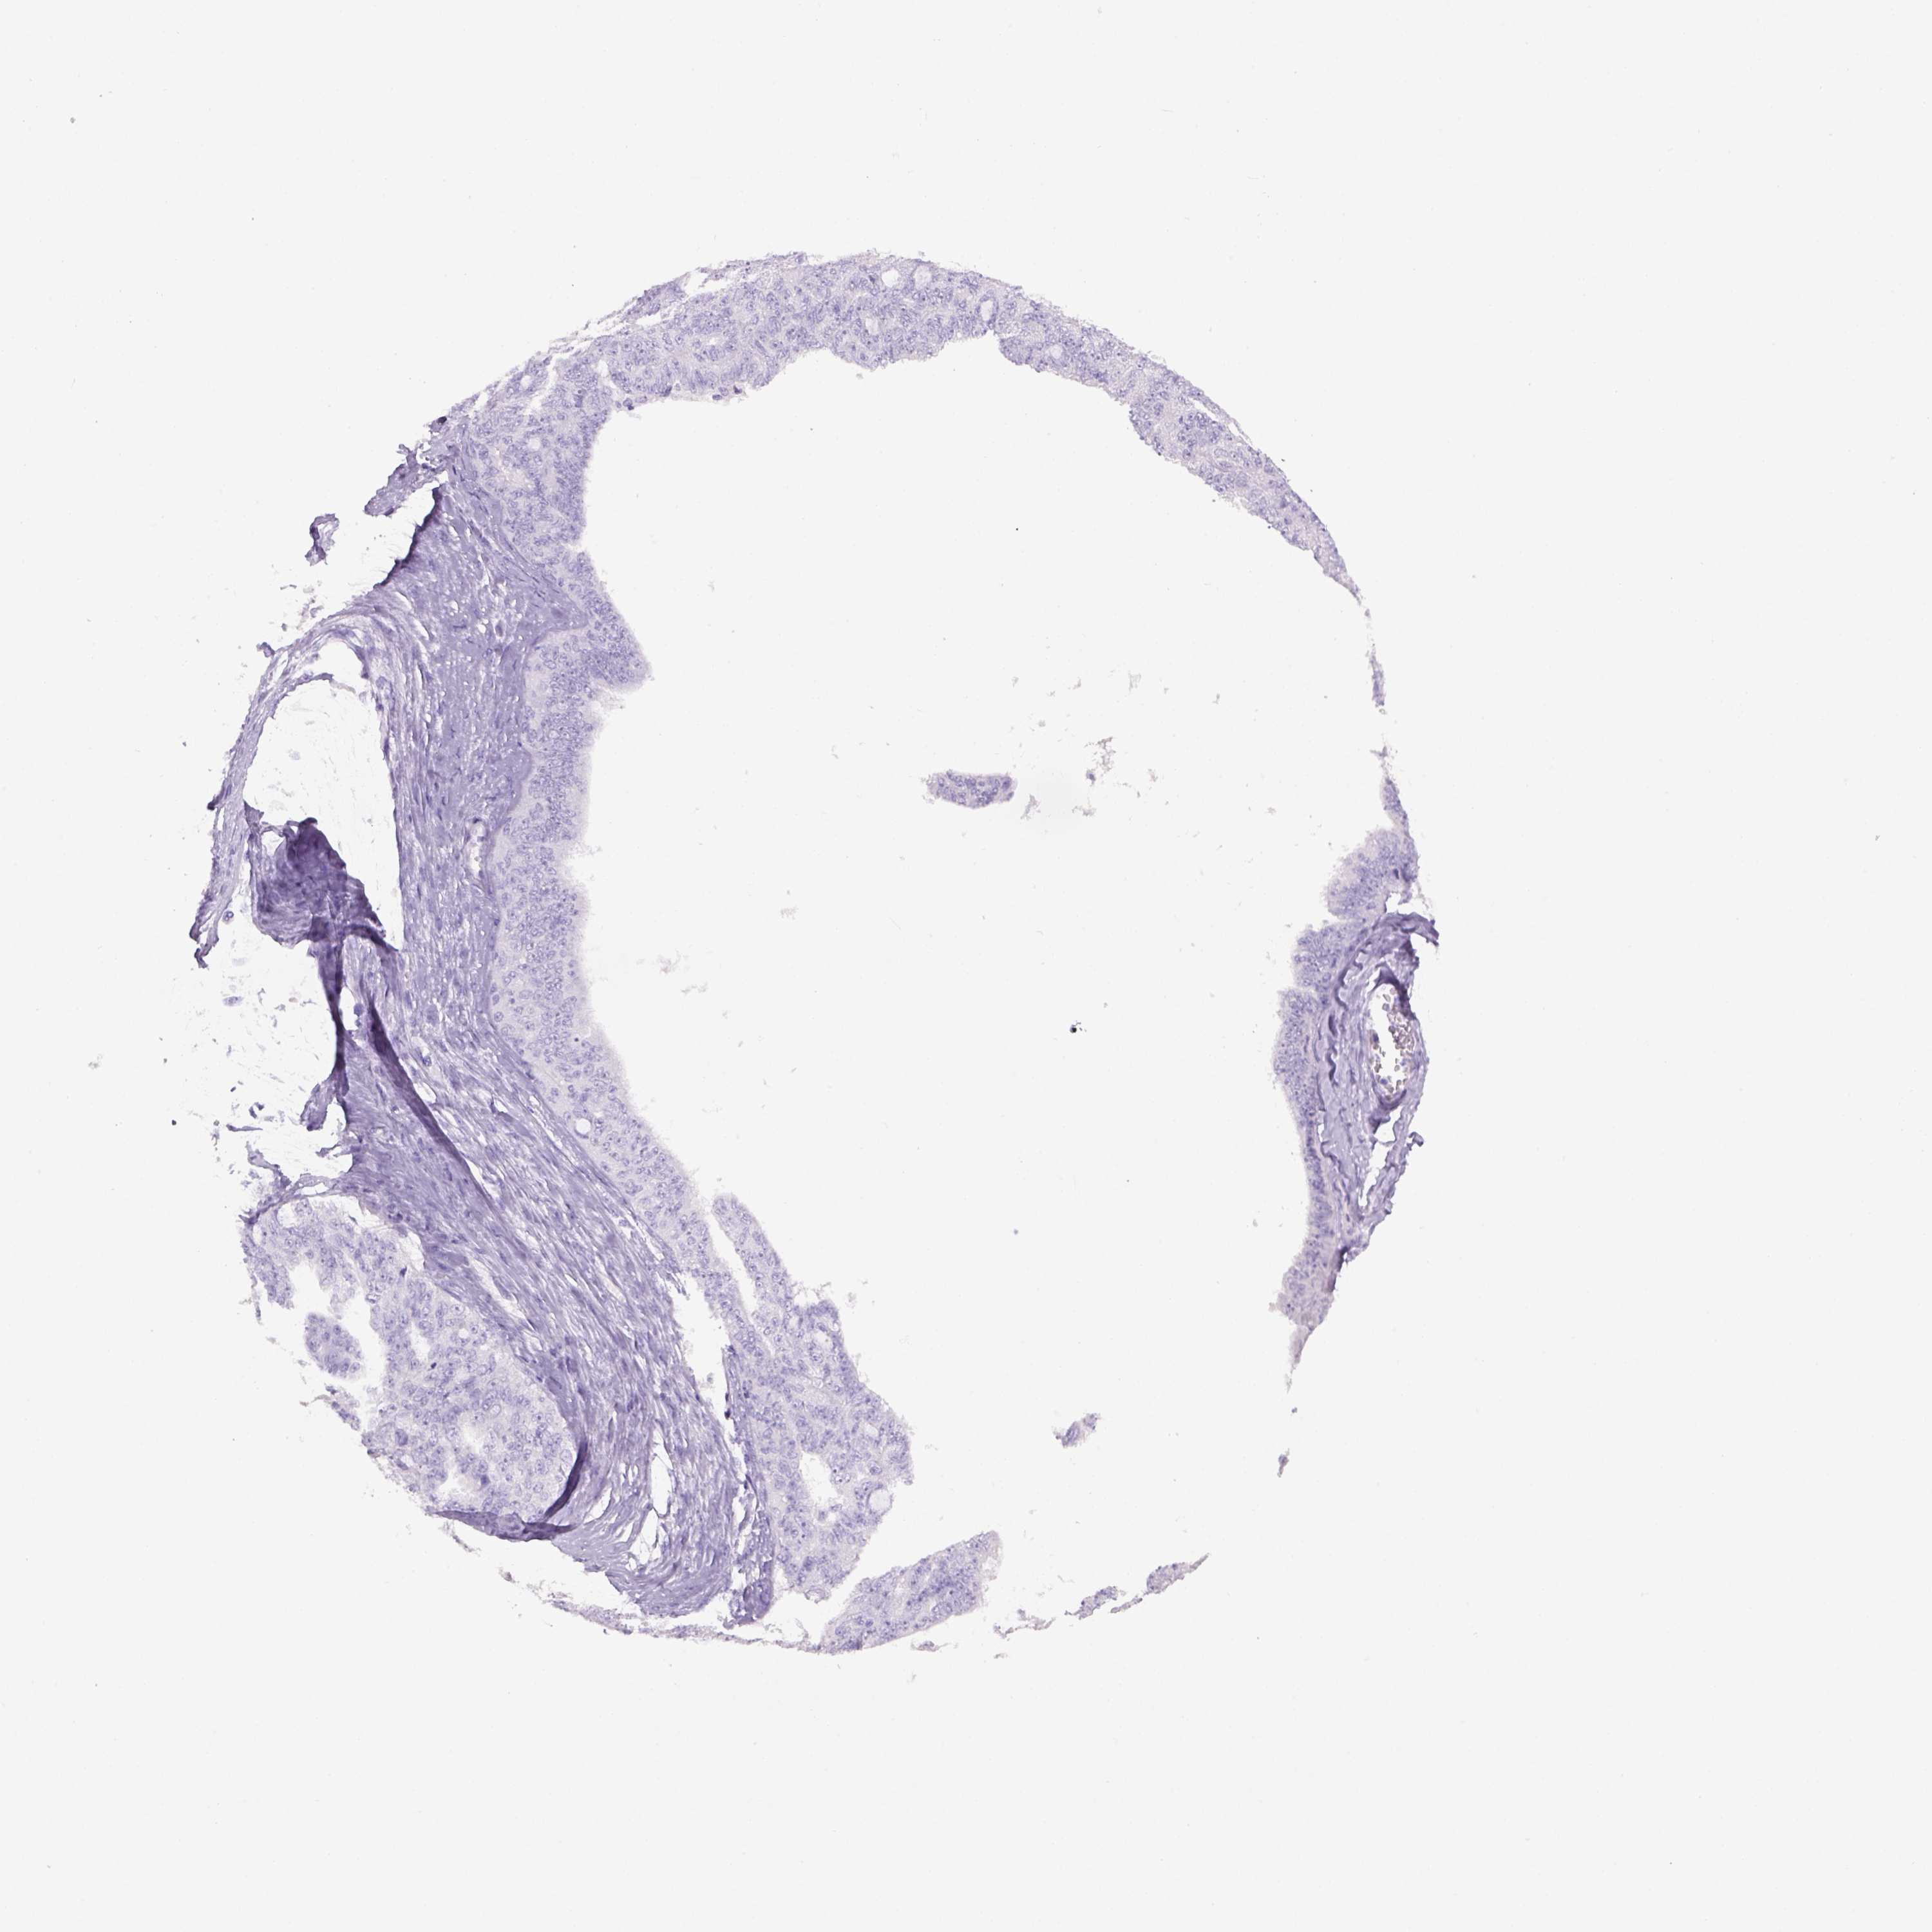

OVARIAN CANCER - Protein expressioni

A mouse-over function shows sample information and annotation data. Click on an image to view it in a full screen mode. Samples can be filtered based on level of antibody staining by selecting one or several of the following categories: high, medium, low and not detected. The assay and annotation is described here.

Note that samples used for immunohistochemistry by the Human Protein Atlas do not correspond to samples in the TCGA dataset.

Antibody stainingi

Antibody staining in the annotated cell types in the current human tissue is reported as not detected, low, medium, or high, based on conventional immunohistochemistry profiling in selected tissues. This score is based on the combination of the staining intensity and fraction of stained cells.

Each image is clickable and will lead to virtual microscopy that enables deeper exploration of all samples and also displays staining intensity scores, fraction scores and subcellular localization as well as patient and tissue information for each sample.

Antibody HPA019521

Antibody HPA065961

Cystadenocarcinoma, serous, NOS

Cystadenocarcinoma, mucinous, NOS

Carcinoma, endometroid